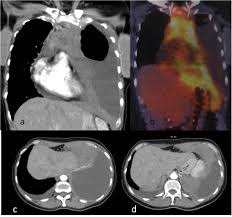

Fdg Pet Ct Images Malignant Pleural Mesothelioma Of The Right Pleural Download Scientific Diagram

Fdg Pet Ct Images Malignant Pleural Mesothelioma Of The Right Pleural Download Scientific Diagram from www.researchgate.net

Doctors can even use it to find out if a tumor has spread to lymph nodes that are far from where the mesothelioma first appeared. Symptoms or abnormalities not consistent with the initial. Introductionmalignant mesothelioma is a neoplasm arising from pleural and peritoneal cells, including pericardium and tunica vaginalis testis, and often characterized by a poor prognosis. pet was positive in 12/14 patients with epithelioid peritoneal mesothelioma. Discuss the advantages and limitations of pet/ct in diagnosis and assessment of therapy. You will need to provide a safe and quiet space for your pet, away from active children or other animals while it recovers. Because treatment options are limited and hope for a full recovery is still something that researchers are working on, a diagnosis of mesothelioma can be discouraging, disheartening and downright devastating for patients and their families. A pet scan picture can give the physician a better idea if the thickening of the pleura seen on a ct scan is cancer or scar tissue.

Malignant pleural mesothelioma (mpm) is the most common, whereas malignant peritoneal mesothelioma accounts only for. Xie peng 1, wang wei 2 & Introductionmalignant mesothelioma is a neoplasm arising from pleural and peritoneal cells, including pericardium and tunica vaginalis testis, and often characterized by a poor prognosis. You will need to provide a safe and quiet space for your pet, away from active children or other animals while it recovers. A pet scan can also be useful if your doctor thinks the cancer may have spread but doesn't know where. Everything you need know mesothelioma life! Early detection of the fatal and incurable mesothelioma and the subsequent provision of radiation, surgical and palliative asbestosis treatments are known to help a patient to have the best possible chance to extend and improve the quality of life remaining. A pet scan is the best method to determine if mesothelioma has spread to other parts of the body. 191 all treatments were planned based on ct and pet/ct imaging. pet/ct is superior to other imaging modalities for evaluation of distant metastatic disease of mpm given its whole. Tongue metastasis was the first sign of malignant pleural mesothelioma detected by pet/ct. During the diagnostic process, imaging tests help identify tumors, tumor location and metastasis of cancer. When a ct scan is performed, patients may also undergo a pet scan.